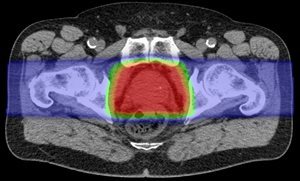

Proton Therapy

Conventional X-Ray Therapy

Red: High Radiation Dose

Green: Intermediate Radiation Dose

Blue: Low Radiation Dose